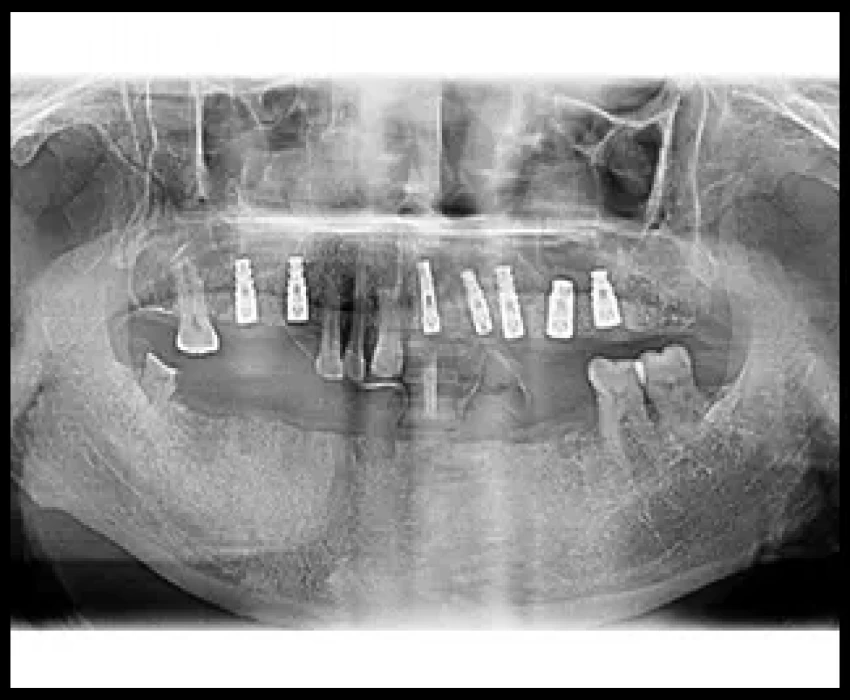

Endosseous dental implants have revolutionized the field of periodontics. During the last decade, a great deal of information has been generated concerning the effectiveness and predictability of endosseous implants. Implant placement is a viable option in the treatment of partial and full edentulism and has become an integral facet of periodontal therapy. The long-term goal of implant therapy is to prevent or to arrest the progression of disease and to achieve a maintainable implant site.

Implant complications can be due to a number of causes including prosthesis instability, implant mobility, occlusal trauma, fractured components, pain, inflammation, infection, and neuropathy.

Peri-implantitis is considered as one of the important postoperative soft tissue complications associated with implant placement. Depending on the severity of the peri-implant bone loss, the morphology of the bone defect and the implant surface, the progression of the disease process can potentially be arrested and in selected cases, the lost bone tissue can be regenerated.